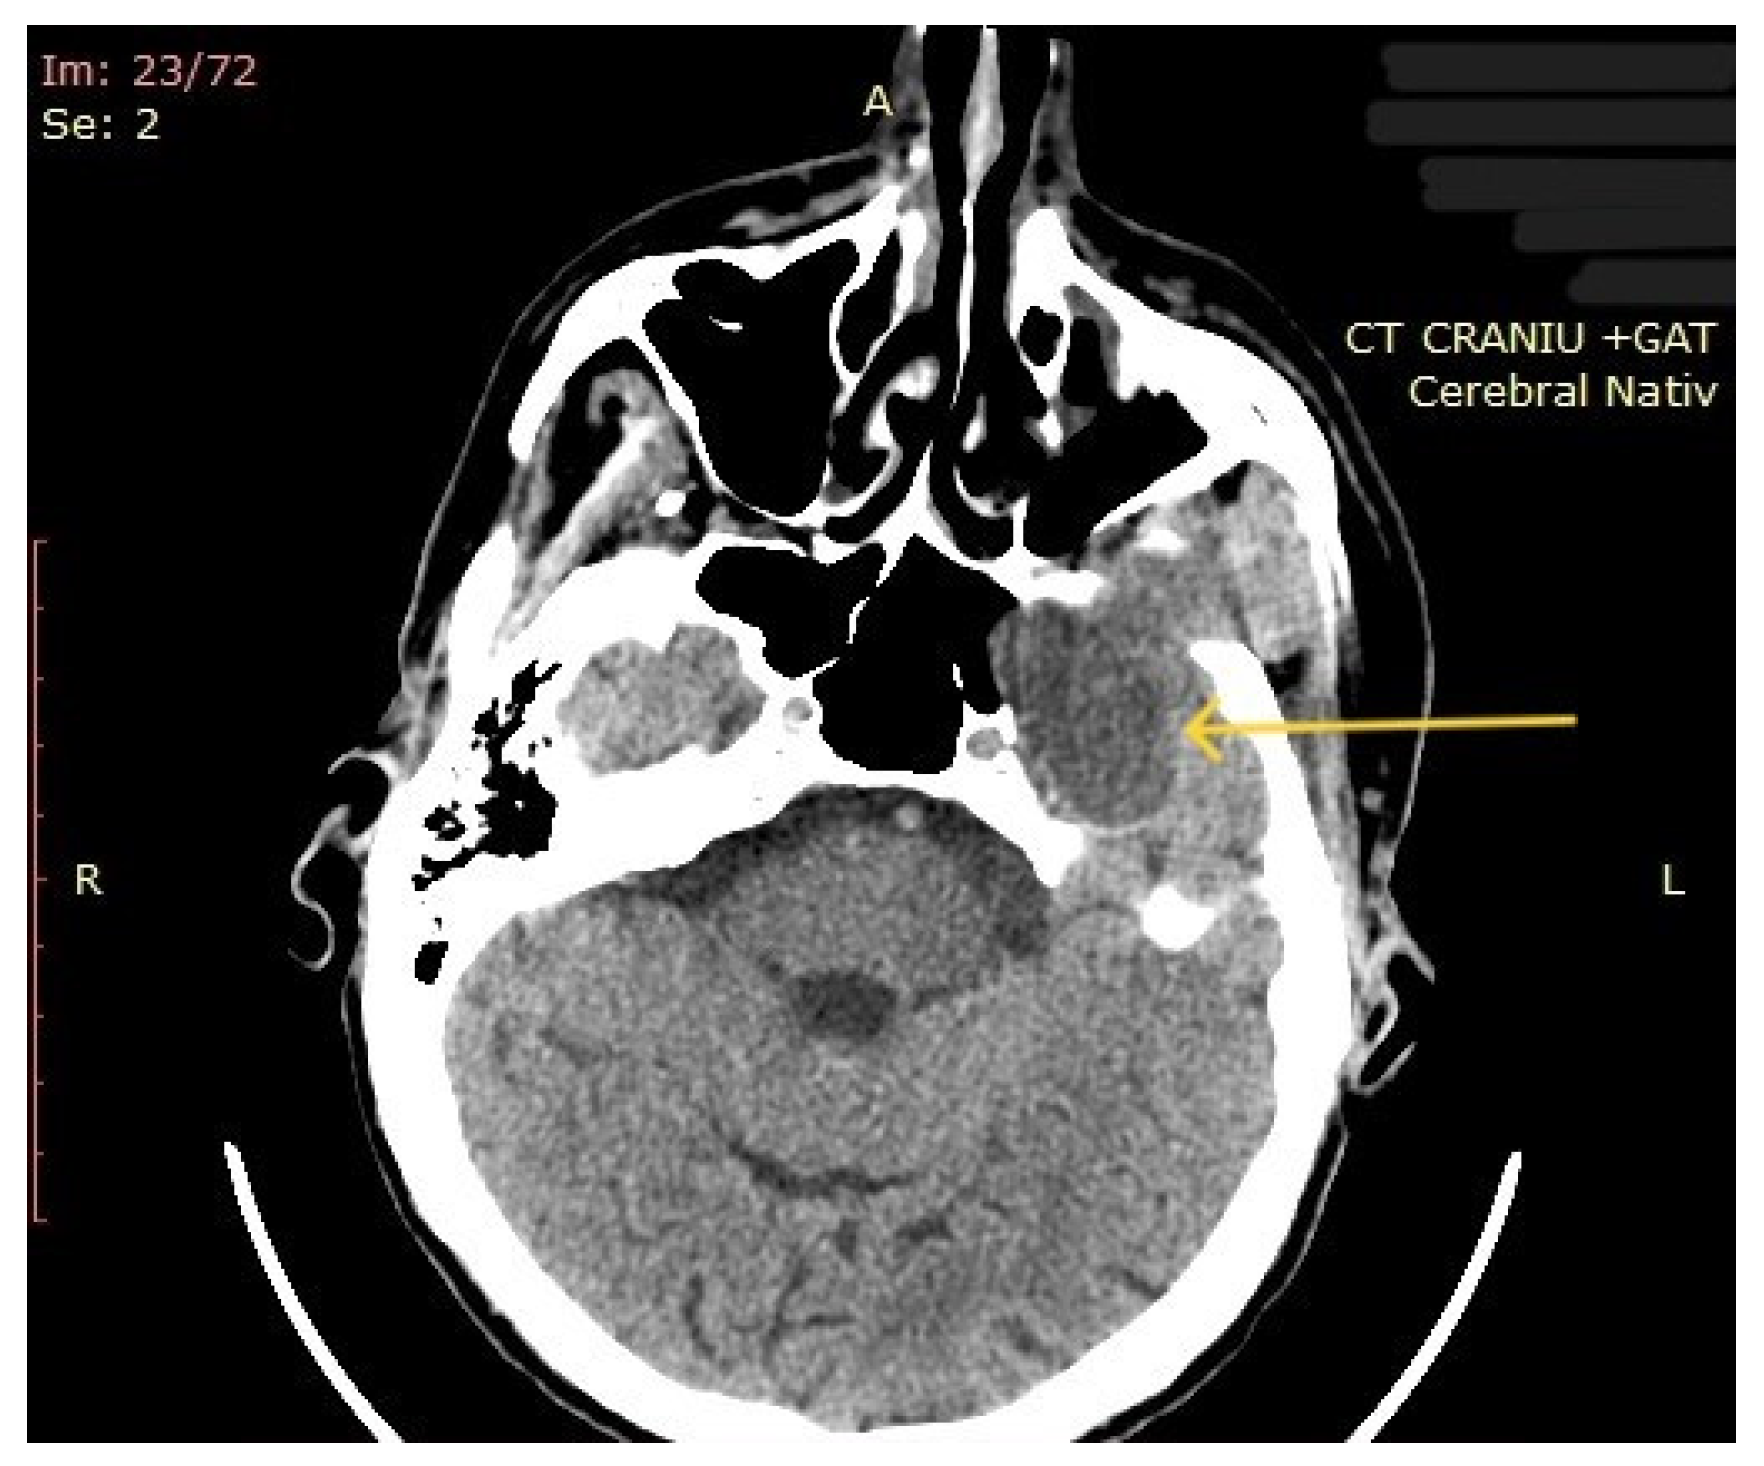

3.2. Imaging Aspects

| 10 | Left parapharyngeal region with maxillary and intracranial extension | Discomfort in breathing, chewing, swallowing, phonation, sleeping, regional pain, fatigue | 5 years | 10 cm | Benign tumor of soft tissue |